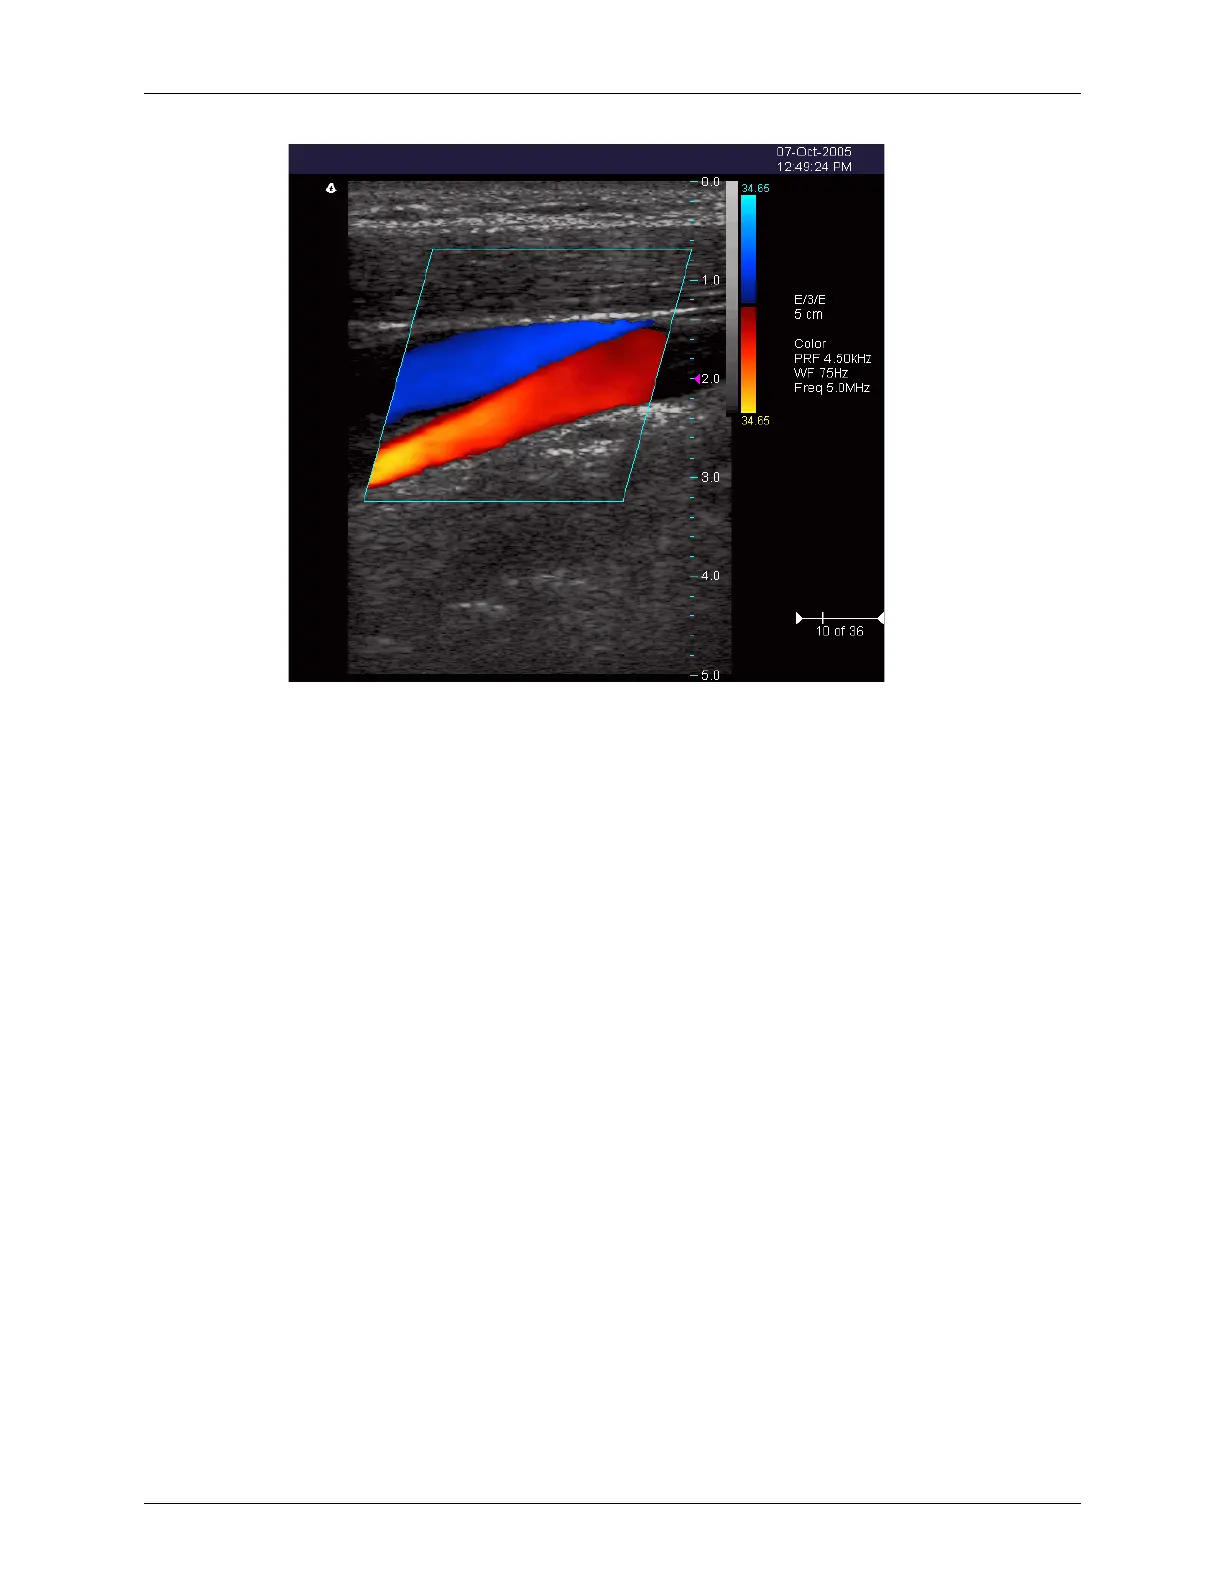

Example Color Doppler Scan

Directional Power Doppler

Directional Power Doppler (DirPwr) is a combination of some features of conventional

Power Doppler and of Color Doppler. It provides the increased sensitivity of conventional

Power Doppler, plus the directional information derived from Color Doppler.

Directional Power Doppler does not provide an estimate of blood flow velocity. The color

palette is proportional to the strength of the Doppler signal. This mode allows you to

obtain good-quality images of deep arteries and other tissue. You can also apply a high

frame rate or high resolution to control the quality of the scan.

The Directional Power Doppler scan data displays in the 2D Image Display window.